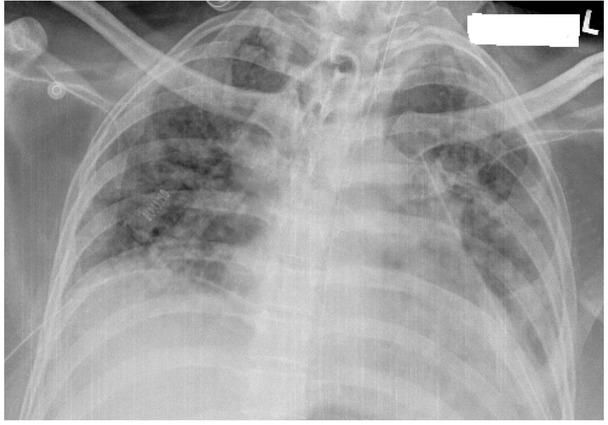

Chest xray showing extensive subcutaneous emphysema under both shoulders and pneumomediastinum.

Complete resolution of above changes post bilateral intercostal drains.